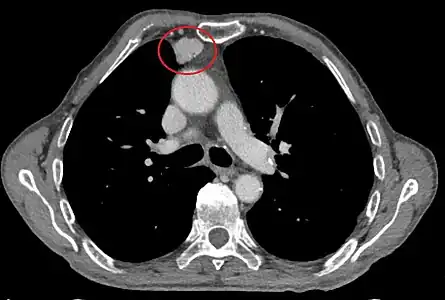

Présentation tomodensitométrique classique d'un thymome à un stade précoce (cercle rouge). À l'arrière, l'aorte, la veine cave supérieure et l'artère pulmonaire sont visibles en coupe.

Présentation tomodensitométrique classique d'un thymome à un stade précoce (cercle rouge). À l'arrière, l'aorte, la veine cave supérieure et l'artère pulmonaire sont visibles en coupe. Scanner injecté, en fenêtre médiastinale, montrant un carcinome thymique envahissant les structures médiastinales :